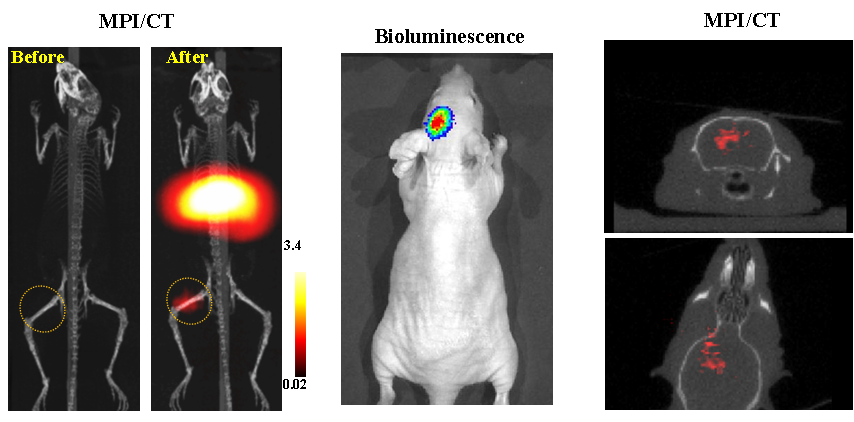

今年二月份,宋国胜教授与斯坦福大学饶江宏教授合作,通过系统的研究获得了影响磁性粒子成像信号的作用规律和关键原理,开发了新型磁性粒子探针---FeCo合金粒子,并首次应用于磁性粒子成像(MPI)。该造影剂在极低含量时(5 ng)仍具有很强的造影效果。这意味着,未来在进行人体成像时,可以使用更小剂量的造影剂,从而避免高剂量造影剂引起的肾肝损伤。基于MPI的直接成像原理,我们可以对造影剂进行正相和无背景干扰的活体成像,极大地提高信噪比。这项技术为肿瘤早期诊断、癌细胞示踪、脑中风、药物输送治疗、肺部灌注成像、胃肠出血、神经退行性疾病、磁热治疗等在活体中的可视化研究,提供了强有力的手段。相关研究成果以 哔咔官网

为第一单位发表在Nature 子刊《Nature Biomedical Engineering》。该期刊是“生物医学工程”的顶级期刊。宋国胜教授为该论文的共同通讯作者。